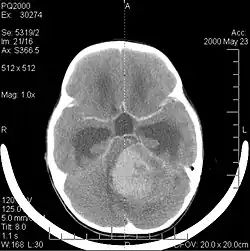

A tomografia computadorizada (TC) e a ressonância magnética (RM) podem detectar efetivamente uma neoplasia no cérebro. A RM é mais sensível que a TC para identificar lesões, mas contraindicações para pacientes com marcapasso cardíaco, próteses incompatíveis, clipes metálicos e outros. A TC continua sendo o método de escolha para detectar calcificações dentro de lesões ou erosões ósseas da calota craniana ou da base. A utilização de agentes de contraste, que são iodados no caso da TC e paramagnéticos ( gadolínio ) no caso da RM, permite a aquisição de informações sobre a vascularização e integridade da barreira hematoencefálica, uma melhor definição do tumor tumoral comparado ao edema circundante e à geração de hipóteses sobre o grau de malignidade . O exame radiológico também permite avaliar os efeitos mecânicos e consequentes alterações nas estruturas cerebrais decorrentes do tumor, como hidrocefalia e hérnias, cujos efeitos podem ser fatais. Finalmente, na preparação para a cirurgia, esse diagnóstico pode ser usado para determinar a localização da lesão ou a infiltração do tumor em áreas vitais do cérebro. Para isso, a RM é mais eficiente que a TC, pois pode fornecer imagens tridimensionais.

A tomografia computadorizada do cérebro normalmente mostra uma massa de tecido que pode ser realçada por qualquer contraste. Na TC, os gliomas de baixo grau geralmente parecem isodensos ao parênquima normal e, portanto, podem não apresentar realce pelo contraste. Da mesma forma, lesões na fossa posterior do crânio são difíceis de identificar na TC. Consequentemente, os resultados dessa tomografia isoladamente nem sempre são suficientes para fins diagnósticos. Em casos duvidosos, o uso da ressonância magnética mais sensível é essencial.

As metástases cerebrais são as neoplasias intracranianas mais comuns em adultos, sendo dez vezes mais comuns que os tumores cerebrais primários. Eles pisam em 20 até 40 por cento dos adultos com câncer e estão associados principalmente ao câncer de pulmão e mama e melanoma . Essas lesões resultam da disseminação de células cancerígenas pela corrente sanguínea e ocorrem mais comumente na junção da substância cinzenta e branca, onde a seção transversal dos vasos sanguíneos se altera, aprisionando embolias de células tumorais . 80 por cento das lesões ocorrem nos hemisférios cerebrais, 15 por cento no cerebelo e 5 por cento no tronco cerebral. Cerca de 80 por cento dos pacientes têm história de câncer sistêmico e 70 por cento têm múltiplas metástases cerebrais.

Avanços significativos foram feitos recentemente no diagnóstico e tratamento dessas lesões, resultando em melhora da sobrevida e controle dos sintomas. O início dos sinais e sintomas é semelhante ao de outras lesões maciças no cérebro. O método diagnóstico de escolha é a ressonância magnética com meio de contraste.